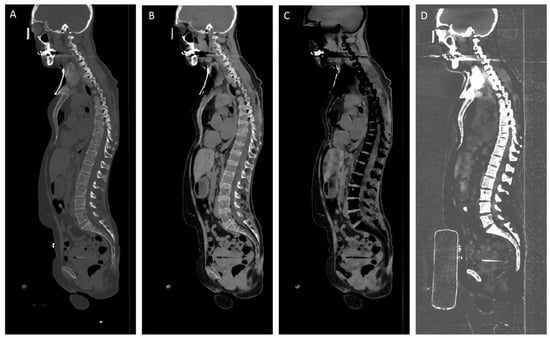

2.3. DLCT Acquisition, Post-Processing and Image Analysis